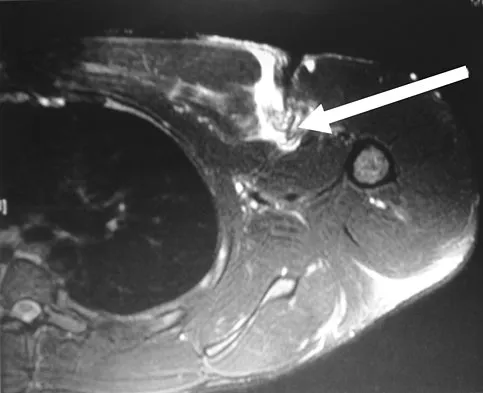

Figure 47 shows a transverse MRI scan of a patient's left shoulder. The findings reveal which of the following abnormalities?

Explanation